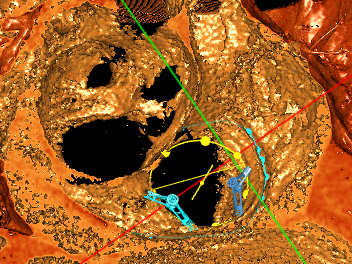

术前手术规划